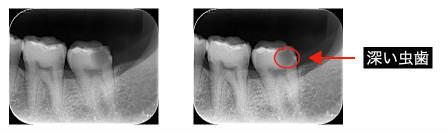

②神経近くまで到達する深い虫歯がある。

虫歯の進行の程度により神経が保存できる状態か診断が必要です。

現在では神経を保存する治療の成功率も高まっていますが成功率は100%ではないので正確な診査診断、術式が必要です。神経を保存する治療が奏功しなかったときには神経を取る処置に移行する場合もあります。